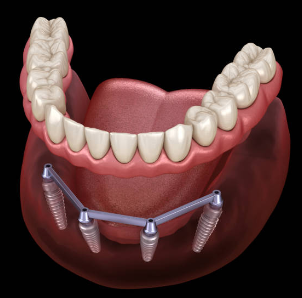

임플란트의 사전적 의미는 다음과 같습니다. 임플란트는 상실된 치아를 인공 치아 이식을 통하여 건강한 구강을 가지게 하는 의학 분야를 뜻합니다.

본래에는 인체의 조직이 상실되었을 때 이를 회복시켜 주는 대체 물질을 의미하지만, 치과에서는 인공 치아 이식의 의미를 지니기도 합니다. 이해를 쉽게 하기 위하여 다시금 말씀드리면, 인공적인 치아를 상실된 치아부위의 잇몸 뼈에 식립을 한 후, 그 위에 인공치아를 장착하여 수복하는 치료 방법을 말하는 것입니다.

임플란트는 자연치아와 같이 신체의 일부로 자리 잡기 때문에, 틀니와 같이 아침/저녁 혹은 주기적으로 넣었다 뺏다 해야 하는 불편함이 따르지 않습니다. 또한, 틀니를 잇몸에 고정하기 위한 접착제 등도 없으며, 임플란트는 자연 치아와 최대한 유사하게 여러분이 좋아하는 음식을 통증 없이 드실 수 있게 해 줍니다.